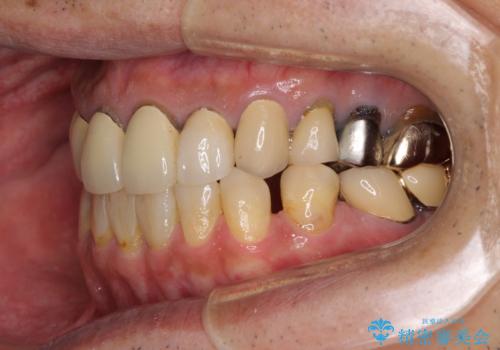

並行して左下にはインプラントを埋入し、上顎臼歯部の気になる部分も根管治療などを進めて行き、矯正治療を終えると同時に補綴治療を行うこととしました。

奥歯1歯分を動かすには時間がかかるため、矯正治療には思いの外時間がかかりました。

痛みのある奥歯は必要に応じて根管治療を行い、左下インプラントは角化歯肉の移植により清掃性を向上させ、気になっていた部分をしっかりと改善させることができました。